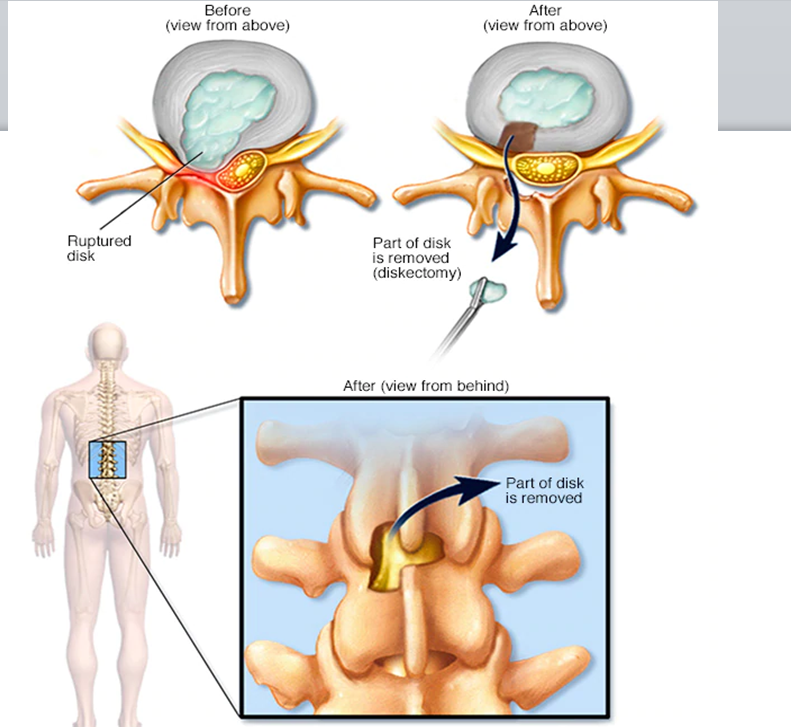

Cervical Myelopathy Expert Care by Dr. Nitish Agrawal – Best Spine Surgeon in Pune Cervical Myelopathy is a serious spinal condition in which the spinal cord in the neck (cervical spine) becomes compressed. This compression is most commonly caused by degenerative changes in the spine, such as cervical disc prolapse,…